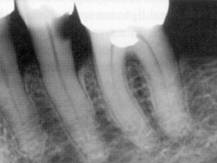

Este o parodontita apicala cronica care se traduce radiologic prin leziuni osoase distructive situate in tesutul osos alveolar din jurul varfului radacinii pe o arie ce nu depaseste 5mm sau pe partea laterala a radacinii, in caz de canale anormale sau de cai false.

Fig. 360 Granulomul dentar

Conturul focarului de osteoliza al granulomului este precis in perioada de liniste si sters in perioada de puseu osteolitic